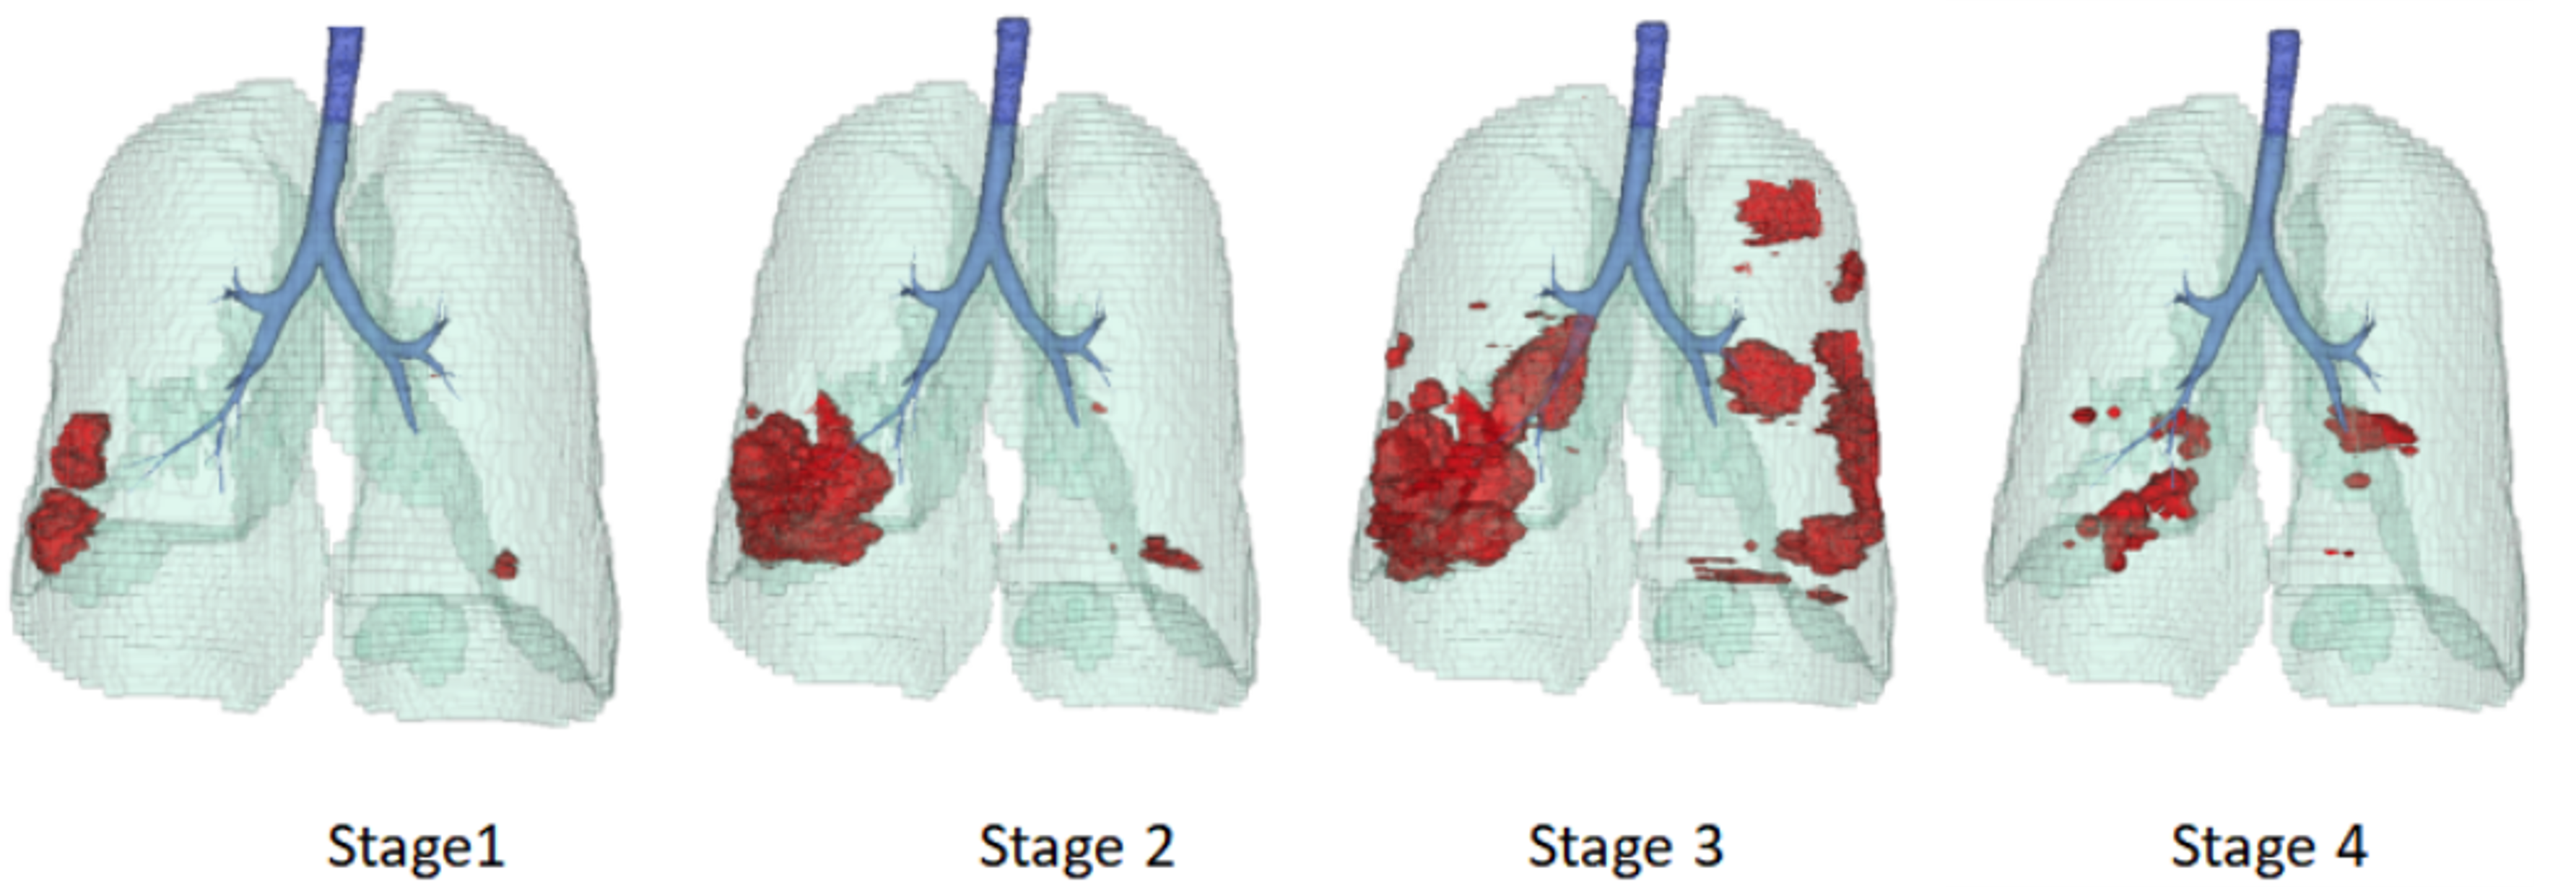

State-of-the-Art Text-prompted Medical Segmentation Models Struggle to Ground Chest CT Findings

Mohammed Baharoon, Luyang Luo*, Michael Moritz, Abhinav Kumar, Sung Eun Kim, Xiaoman Zhang, Miao Zhu, Kent Kleinschmidt, Sri Sai Dinesh Jaliparthi, Sathvik Suryadevara, Rithvik Akula, Mark Marino, Wenhui Lei, Ibrahim Ethem Hamamci, Pranav Rajpurkar

Machine Learning for Healthcare (MLHC), 2025